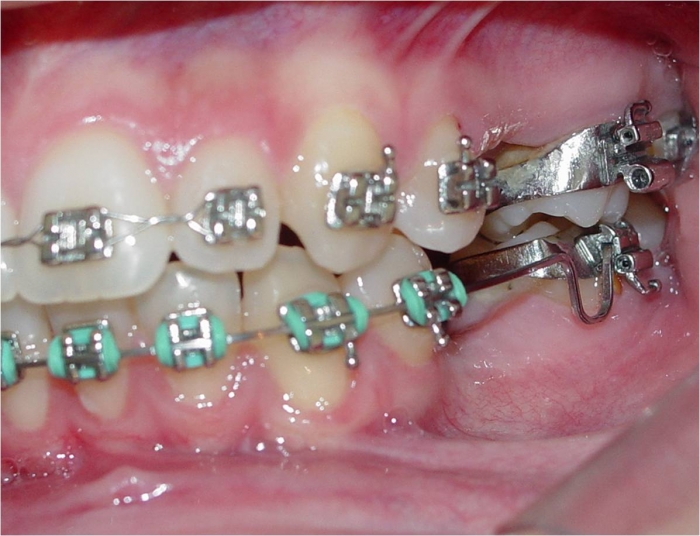

Imagem inicial